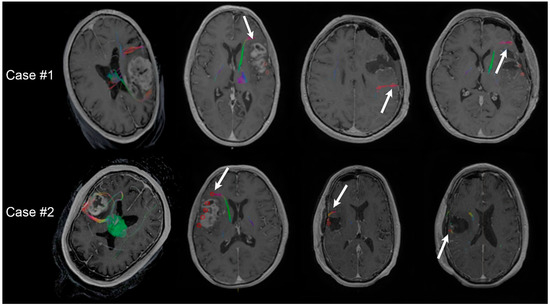

2.3. Perioperative Overlays